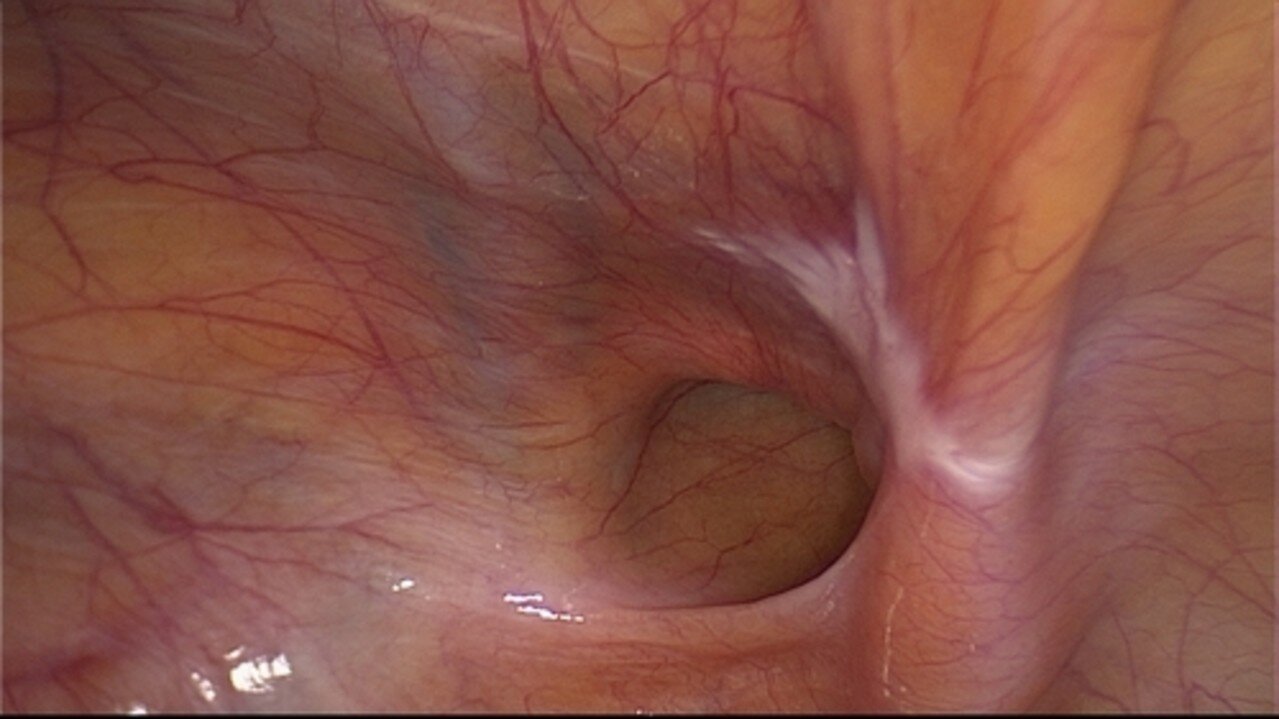

(TAPP = Transabdominelle präperitoneale Hernioplastik)

Bei dieser Methode wird ein Kunststoffnetz zwischen Bauchfell und Bauchwand eingebracht, das die Bruchlücke im Bereich des Leistenkanales abdeckt. Der eigentliche Leistenkanal bleibt dabei unberührt, d. h. die dynamischen Verschiebeschichten im Bereich der Muskulatur werden nicht beeinträchtigt, da die Anatomie der Leistenregion unberührt bleibt. Der Eingriff wird immer in Vollnarkose durchgeführt, das eingebrachte Netz ist selbsthaftend und muss nicht mit Klammern oder Nähten fixiert werden. Dadurch ist die Wahrscheinlichkeit einer Nervenirritation minimal. Nach dem Eingriff können Sie sich nach wenigen Tagen uneingeschränkt bewegen und voll belasten. Dieses Verfahren eignet sich auch insbesondere bei der Behandlung der "Sportlerleiste", wo wir ebenfalls große Erfahrung aufweisen. Bei diesem Eingriff empfehlen wir einen Überwachungstag auf unserer Station - am Tag nach der Operation können Sie die Klinik wieder verlassen. In Ausnahmefällen ist dieser Eingriff auch ambulant möglich.